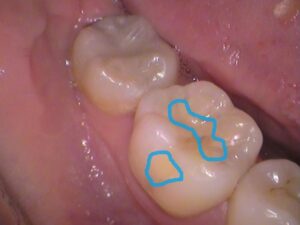

その②詰め物の隙間の黒

今度はこちらの矢印の歯ですが、

まだら模様の様に黒い筋があります。

こちらは詰め物をした箇所に着色が入り込んでいます。

以前、レジンというプラスティック樹脂で詰め物がしてある歯なのですが、詰め物と歯との接着が剥がれ、その隙間に着色が入り込んでいます。

そのため詰め物の形に沿って黒い筋となって見えています。

治療が必要ないかというと一概に言えず、先ほどの「歯の溝」と違い人工的な隙間となっているため虫歯が入り込んでいる可能性もあります。

エックス線検査(レントゲン検査)など専門的な検査を行い、虫歯を確認しましょう。

(※着色ですが歯の内部で虫歯になっている可能性があります。

すべて自己判断せず歯医者さんでみてもらいましょう)